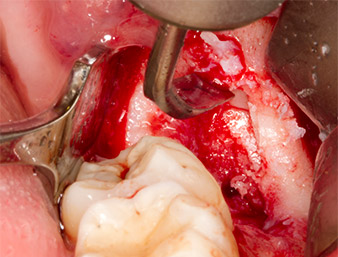

After block and local anaesthesia, the operating site was opened up and the soft tissue exposed for buccal retromolar access (Fig. 3).

The tissue above the root remnant was not completely ossified and consisted for the most part of granulation tissue modified by inflammation (Fig.4).